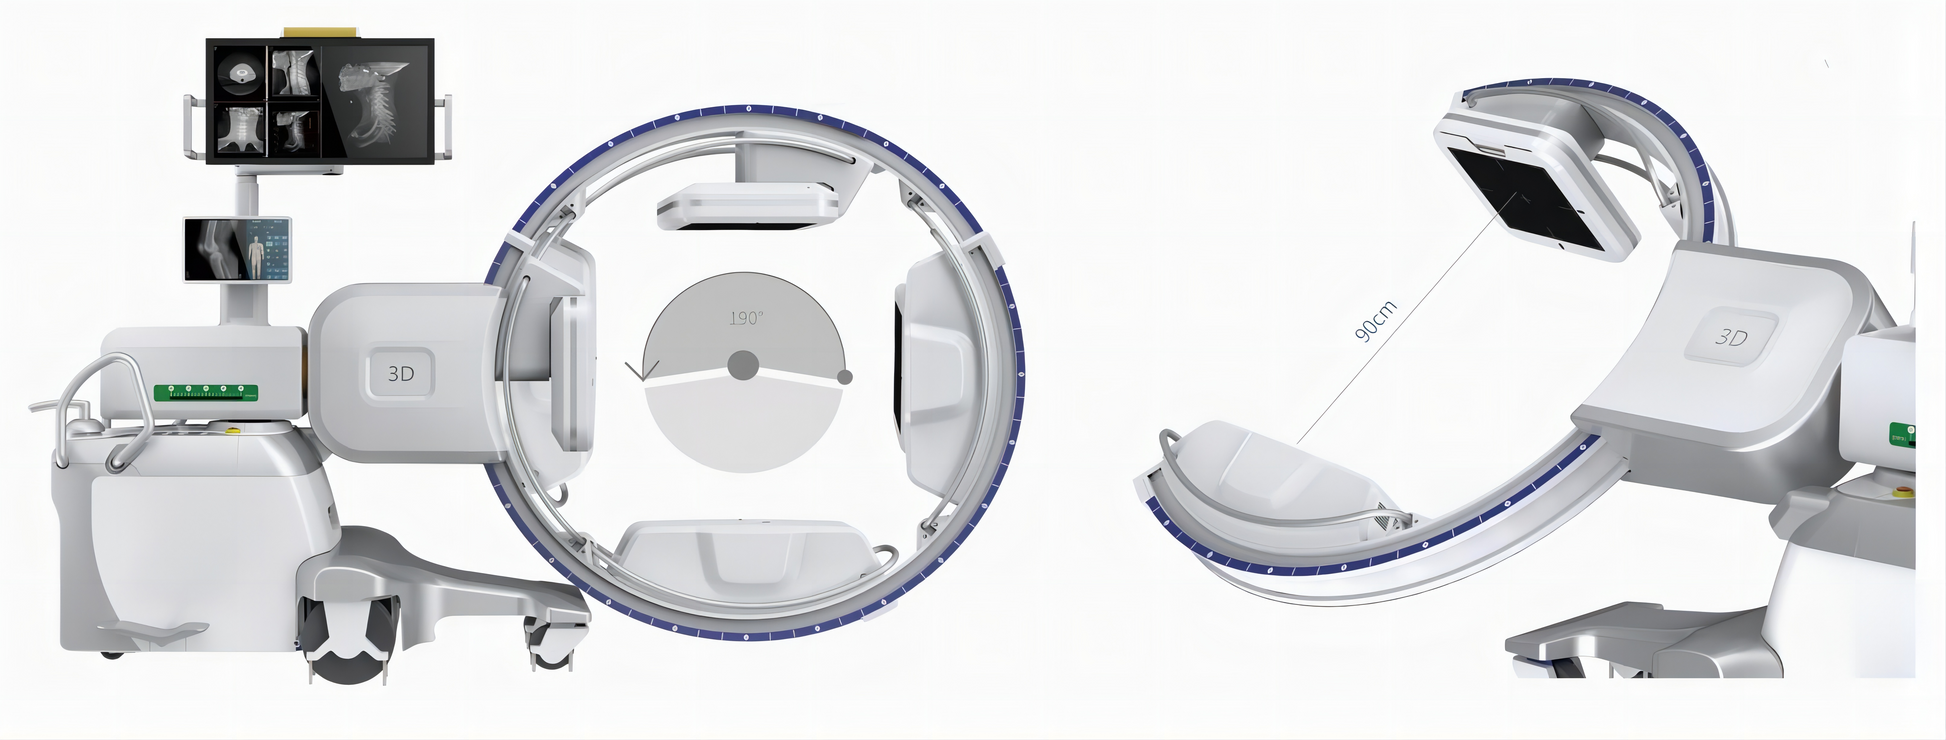

5. Isocentric Rack Design

GHM-750 adopts isocentric design, providing a larger opening space (90cm) suitable for the requirements of various clinical positions. The design avoids the movement of the C-arm frame in the horizontal and vertical directions during 3D image acquisition, and always keeps the exposed part in the X-ray’s center, which reduces motion artifacts andimproves image clarity.